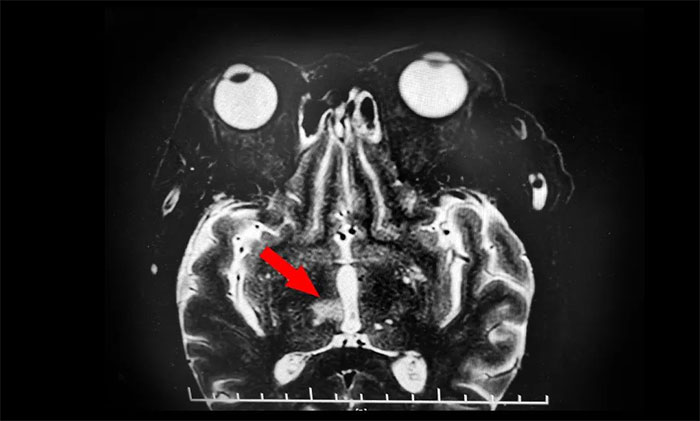

山重水复疑无路,柳暗花明又一村。随后,为了进一步明确患者视力不清及动眼神经损伤性质,张静波主任决定为患者行眼眶核磁共振检查。最终,患者眼框核磁发现端倪。患者眼眶核磁回报患者脑干、丘脑梗塞灶。

再次行MR头颅MRI平扫+增强+DWI+MRA,提示脑干、右侧丘脑及双侧大脑半球白质多发梗塞灶及缺血灶(中脑及右侧丘脑梗塞急性期),右侧大脑后动脉狭窄,右MCA-M1段狭窄。至此,该患者双侧动眼神经损伤原因诊断明确,病因为右侧中脑梗死所致,责任血管为右PCA-P1的狭窄致中脑旁正中动脉闭塞,为动眼红核综合征,导致同侧动眼神经麻痹伴对侧肢体共济失调,同时累及右丘脑旁正中动脉。

▲ 眼眶核磁发现脑干、丘脑梗塞灶